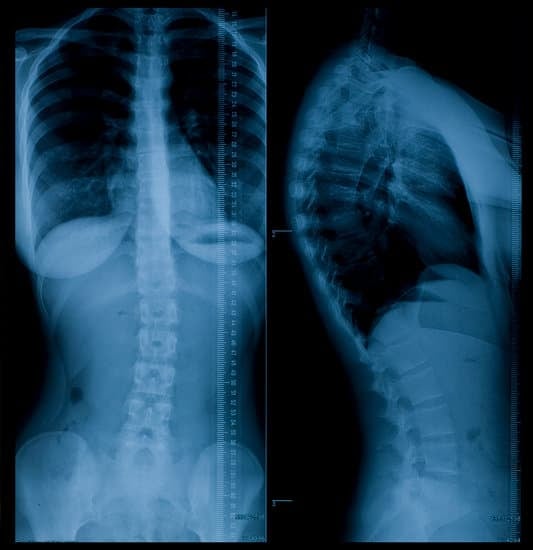

흉요추 골절의 진단

흉요추 골절은 의료 전문가의 평가와 영상 검사를 통해 진단됩니다.

X선 검사: 척추뼈의 골절 여부를 확인할 수 있습니다.

CT 스캔: 더 정밀한 영상으로 골절의 형태와 범위를 파악할 수 있습니다.

MRI: 척수와 신경 손상 여부를 확인하기 위해 시행됩니다.